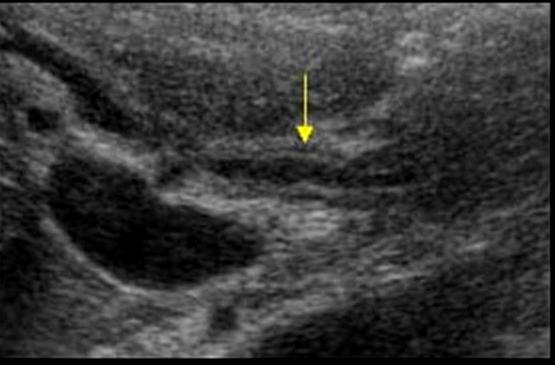

Cholangiocarcinoma

typically originate within the extrahepatic bile ducts

Jaundice

weight loss

abdominal pain